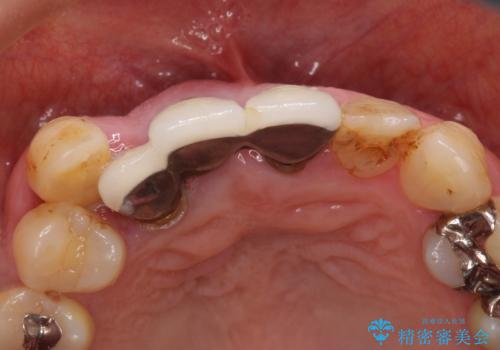

治療の順序は

①保存不可の歯の抜歯・根管治療

②矯正治療

③セラミックの装着

という流れで行いました。